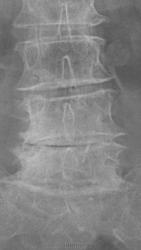

Вот такой пример.....Женщина 72 лет. Жалобы на резкие боли при малейшем движении. Передвигается с трудом.

Как поступить тут? Только описать изменения? Дать собственные выводы?

А проблемы с суставами? - это ведь из третьей оперы...